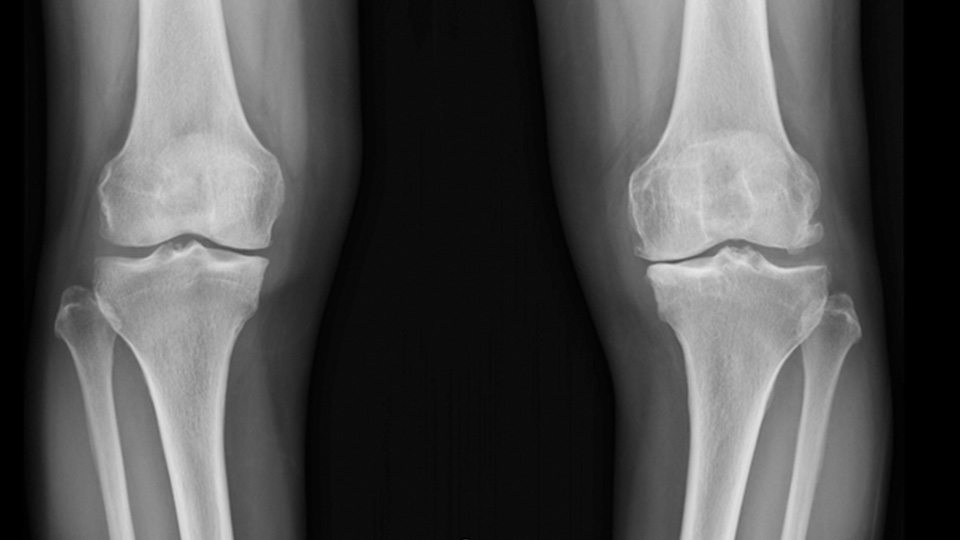

수술전 MRI 소견으로 전방십자인대가 대퇴골부착 부위에서 파열되어 떨어진 소견을 확인할 수 있다.

- 환자 동의하에 게시된 이미지입니다.